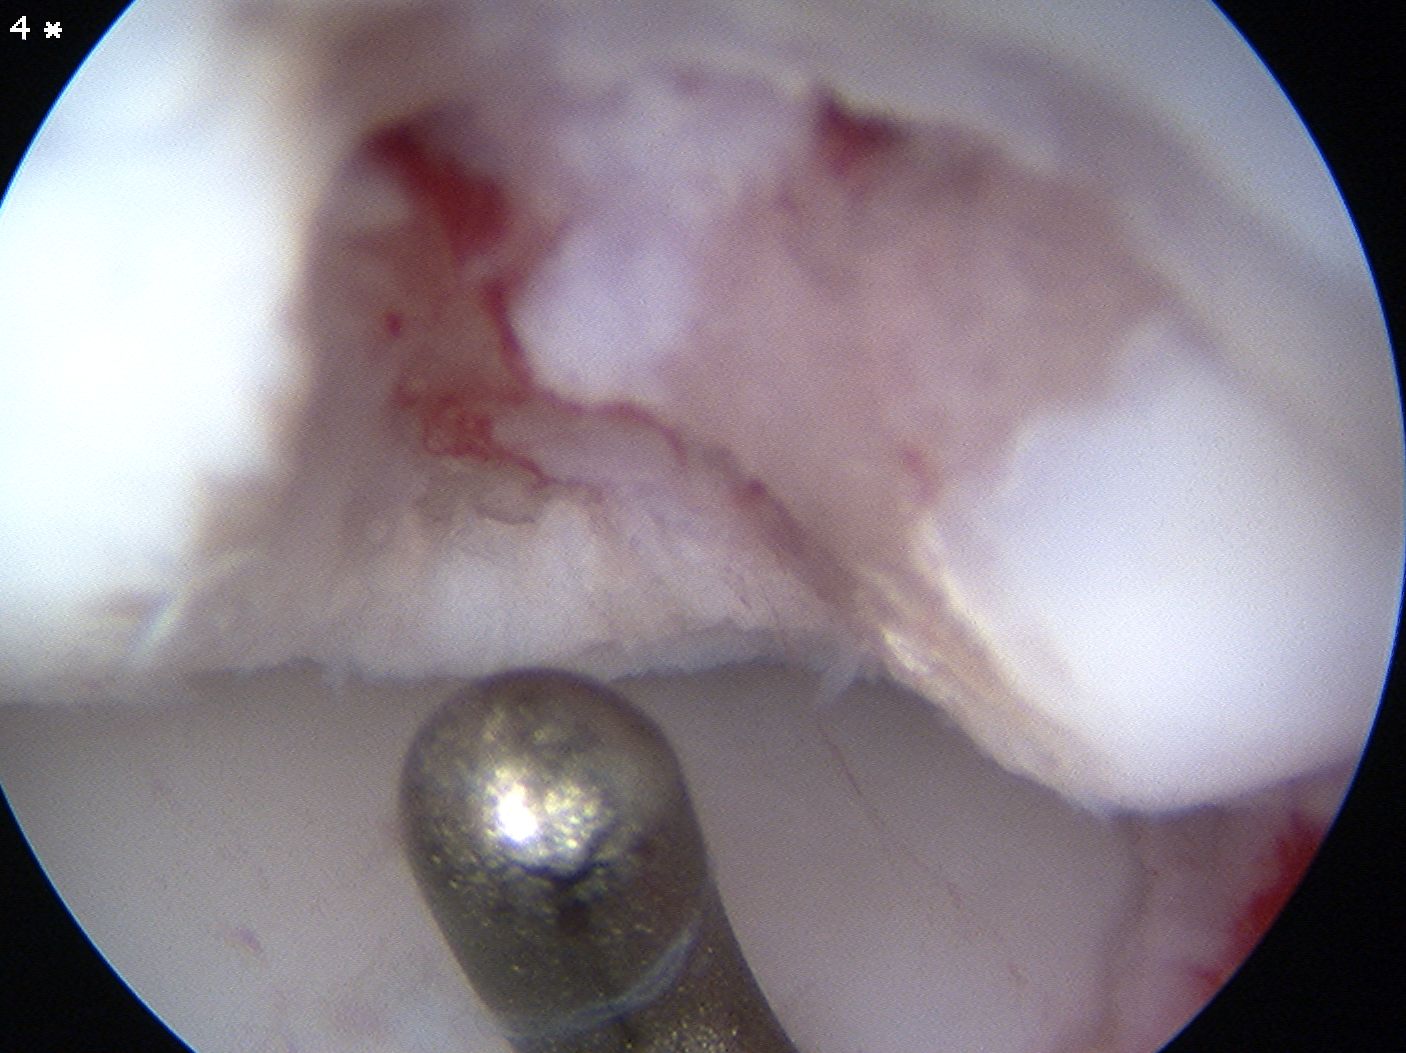

Arthroscopic debridement of loose fragments and microfracture

Arthroscopic debridement of loose fragments and abrasionplasty

Capitellar Osteochondral Defects

Mosaicplasty

Indications

Unsalvageable OCD

Loose body

Failed arthroscopic debridement and marrow stimulation

Technique

Osteochondral plugs from lateral femoral condyle of knee

Anconeus split approach